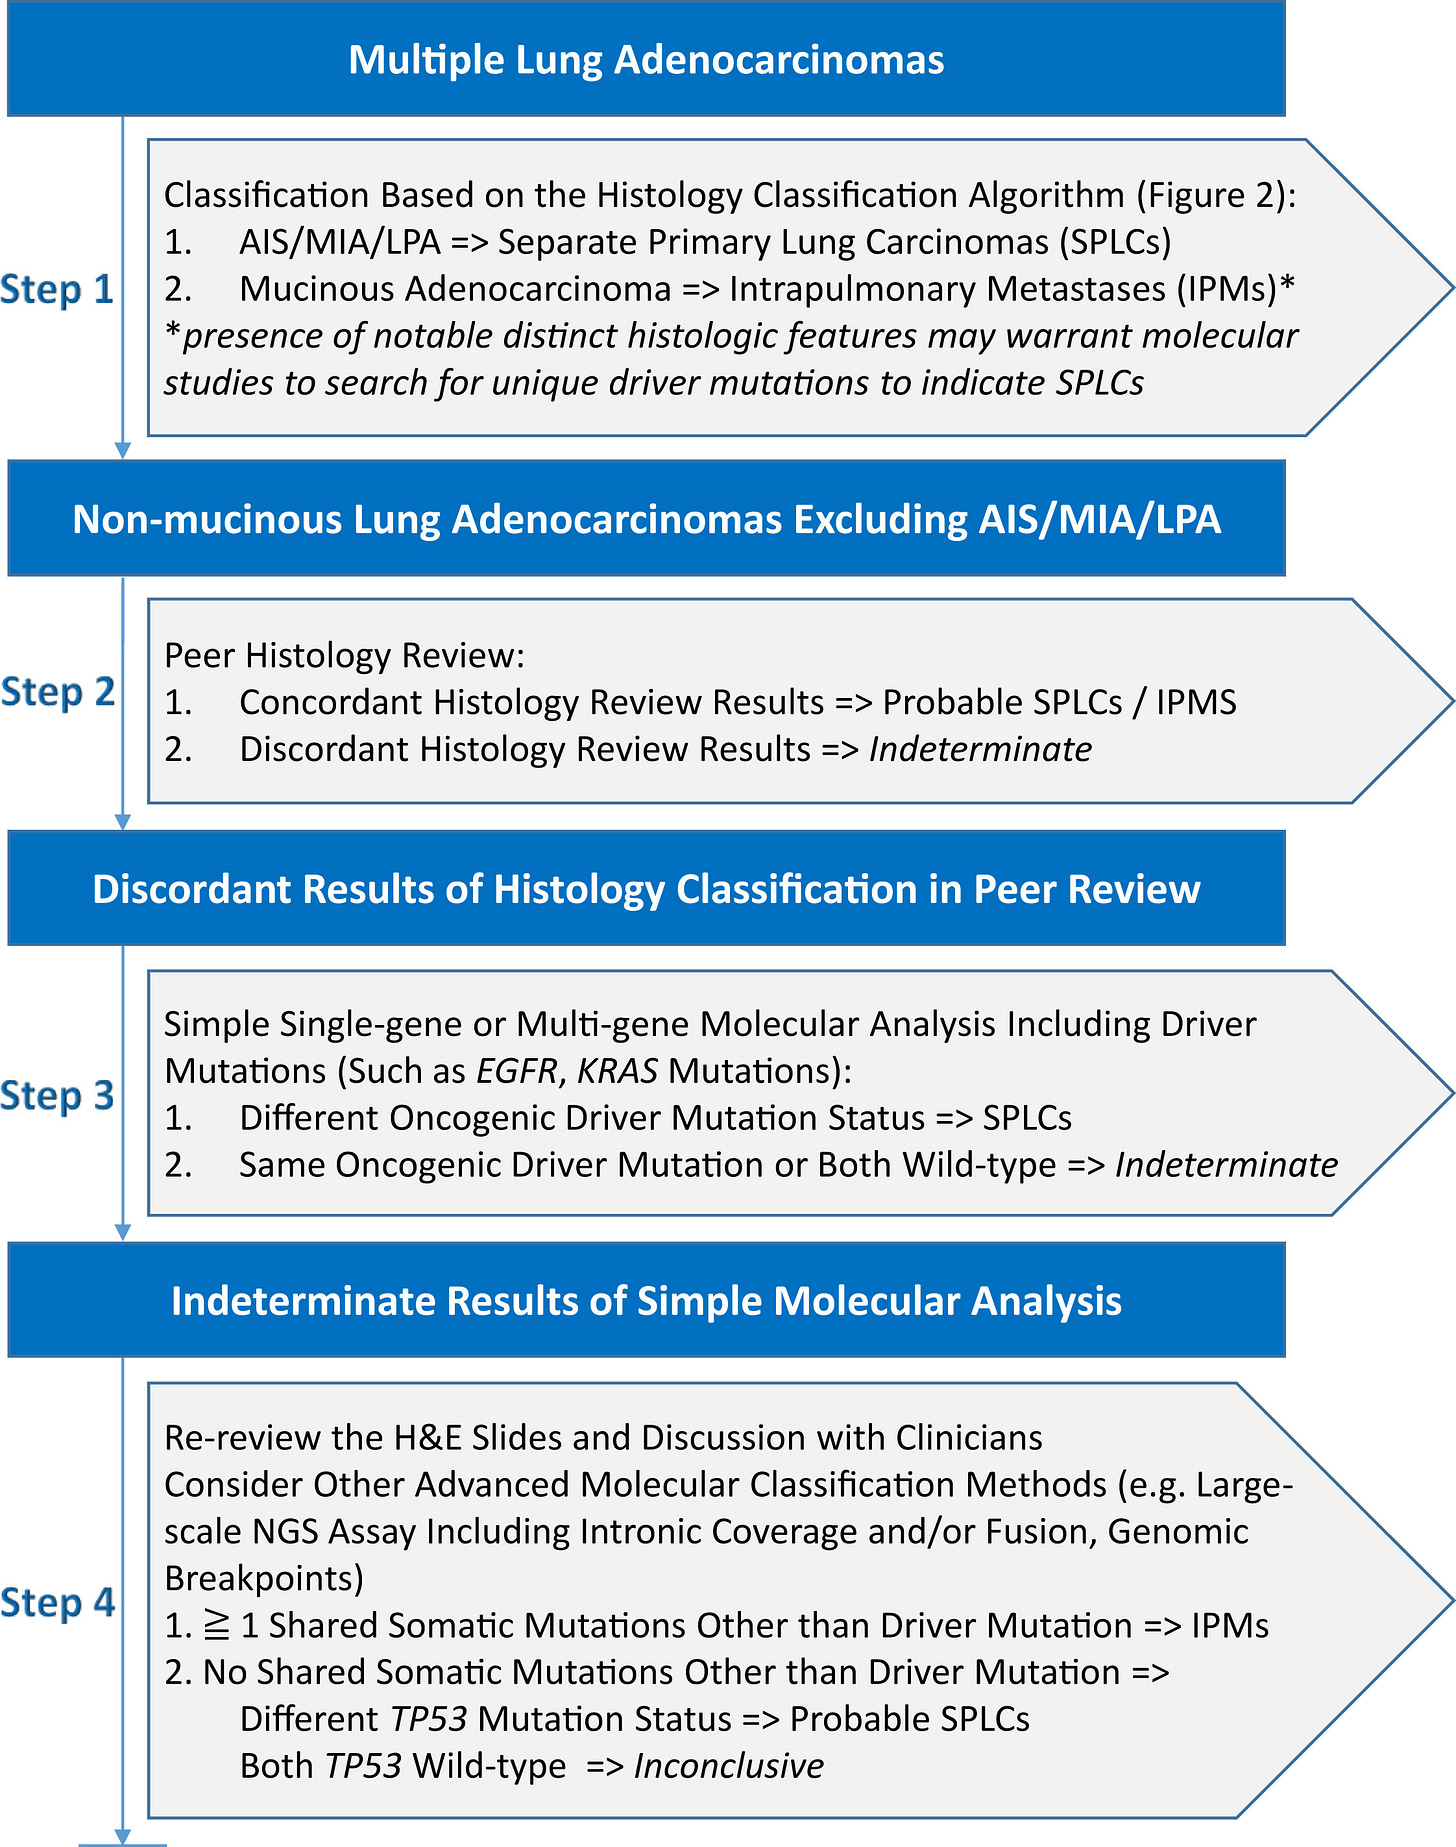

📑 Nový 4-stupňový algoritmus od IASLC

Medzinárodná asociácia pre štúdium rakoviny pľúc (IASLC) navrhuje štruktúrovaný algoritmus, ktorý kombinuje histologické a molekulárne prístupy:

Počiatočné histologické hodnotenie na základe štruktúry a cytológie nádoru.

Posúdenie histologických výsledkov inými patológmi („peer review”), ak sú v nich nezrovnalosti.

Jednoduchá molekulárna analýza na identifikáciu hlavných mutácií.

Pokročilé molekulárne techniky, ako NGS, pre riešenie nejasných prípadov.